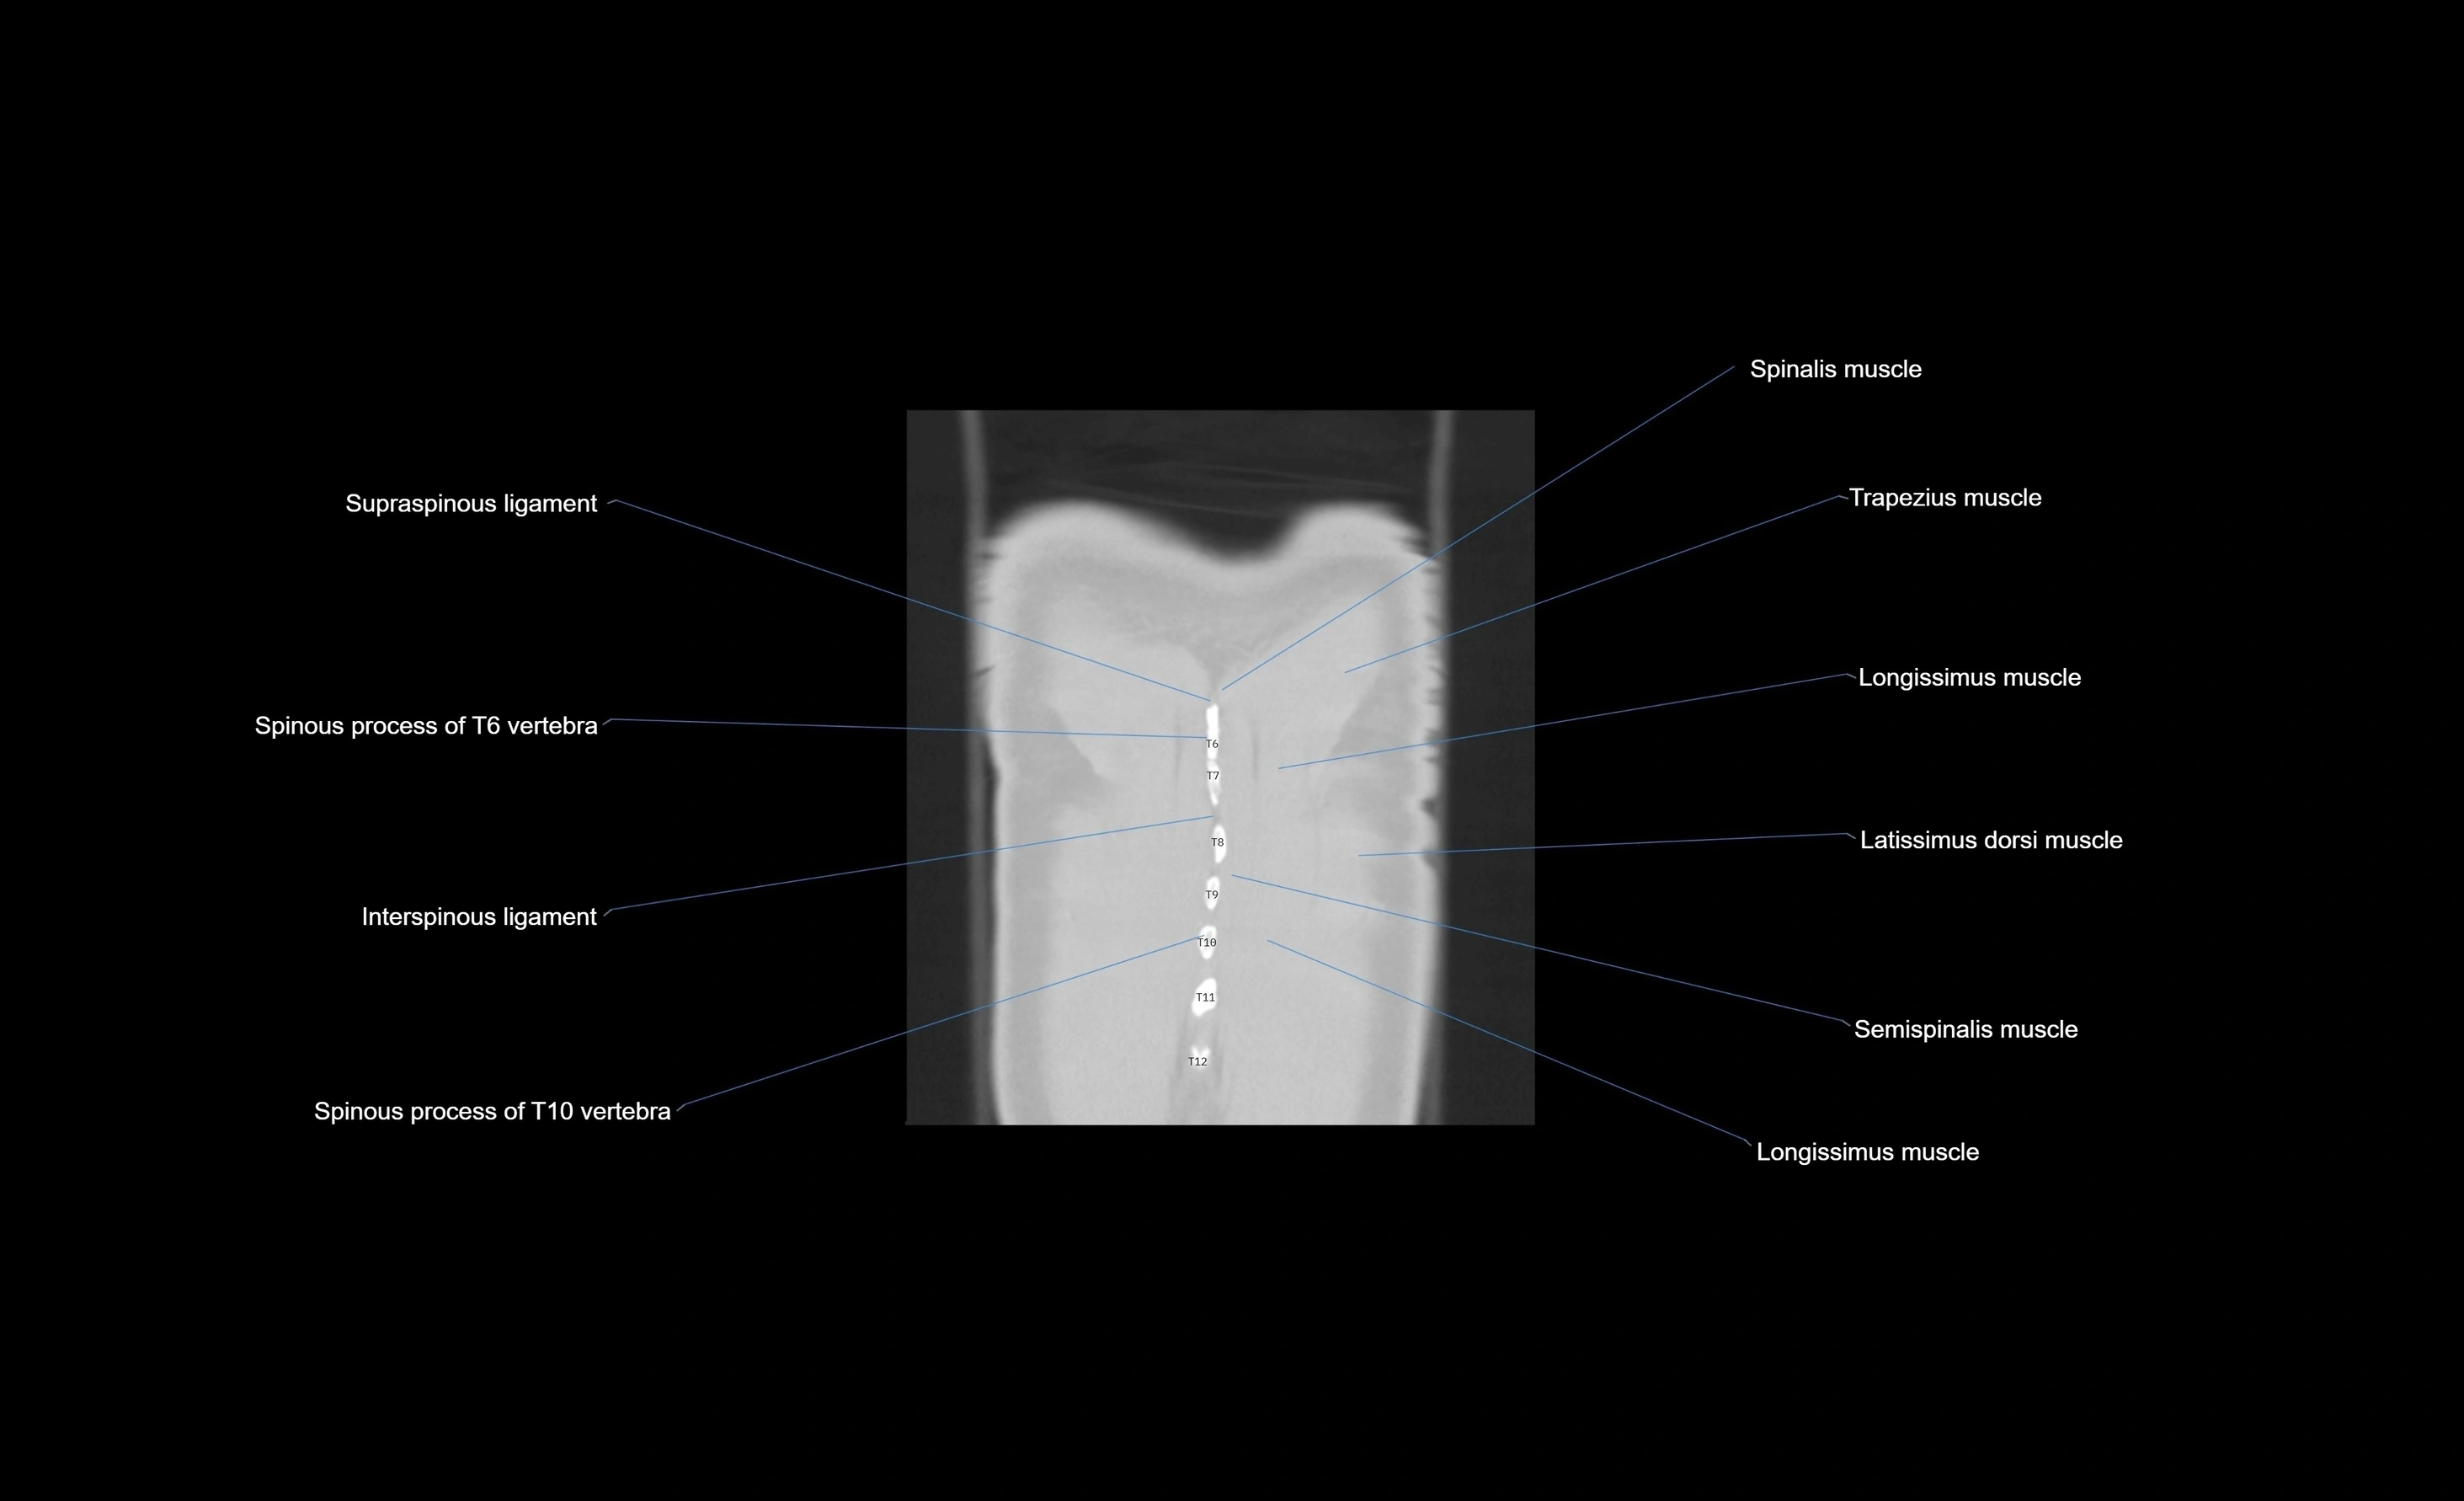

- T (Thoracic spine)